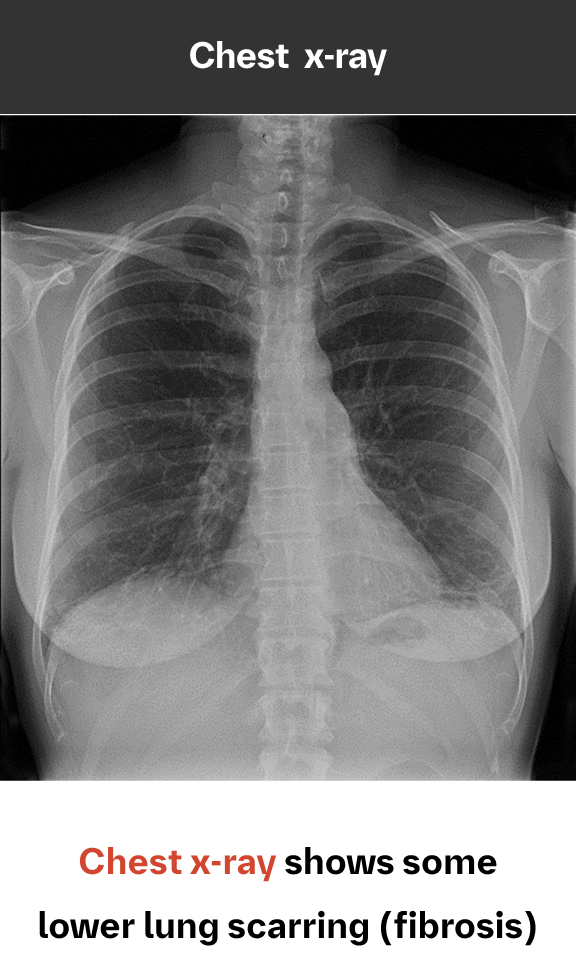

While chest x-ray is not sensitive for ILD diagnosis, it can play a role in identification9,10

Because HRCT provides a more accurate picture of the lungs than chest x-ray, it is considered the standard in diagnosing ILD. However, chest x-ray can detect pulmonary abnormalities and complications, and may even show signs of ILD prior to the development of symptoms or physiological impairment.

An abnormal chest x-ray is often the first indication of ILD

Case study used with permission from the American Thoracic Society.

Image and case study courtesy of, and used with permission from, Lydia Chelala, MD.Findings on chest x-rays suggestive of ILD may include features of interstitial changes and/or airspace disease, such as10-12:

- Reticular lines or scarring

- Volume loss, hilar retraction, or architectural distortion

- Honeycombing

- Nodules

- Ground-glass opacification or air bronchograms

- Cysts or cystic change